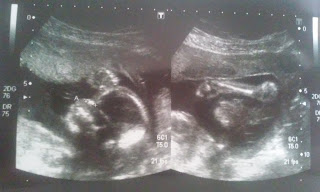

E agora umas fotos da ecografia (para quem não viu) e outras!